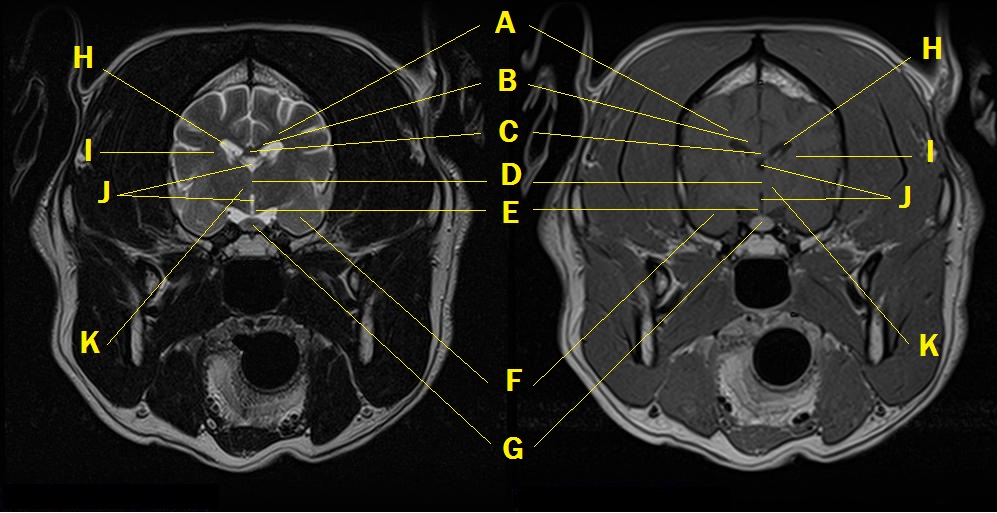

MRI anatomy 4

Q. Identify the structures labeled below:

A. centrum semiovale

B. corpus callosum

C. body of the fornix

D. rostral commissure into interthalamic adhesion

E. hypothalamus

F. amygdaloid body in piriform lobe

G. pituitary gland

H. lateral ventricle

I. internal capsule

J. third ventricle

K. thalamus